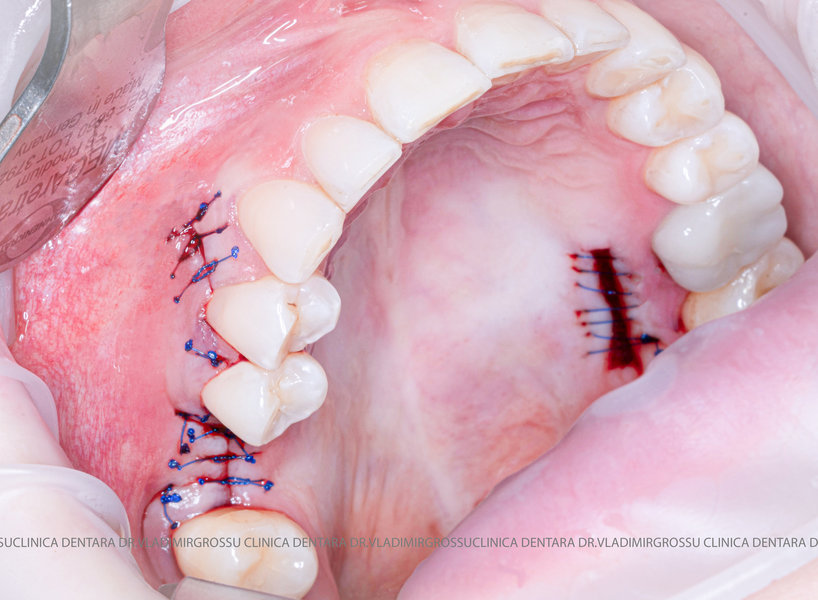

Un element esențial în procedura de aditie osoasă este utilizarea membranelor biologice, care izolează materialul osos de țesuturile moi (gingie) pe durata procesului de vindecare. Cele mai recomandate sunt membranele resorbabile din colagen sau pericard.

Aditia gingivală este o procedură chirurgicală ce corectează diverse probleme estetice și funcționale, cum ar fi recesiunea gingivală. În implantologia modernă, aditia de țesut moale este utilizată aproape în fiecare intervenție de inserție a implantului dentar pentru a asigura un aspect estetic natural și o bună integrare a implantului în cavitatea bucală.

Adiția osoasă are un rol crucial pentru poziționarea corectă și stabilă a implanturilor dentare. Clinica stomatologică Dr. Grossu din Chișinău promovează o abordare chirurgicală estetică și predictibilă, adaptată fiecărui caz în parte.